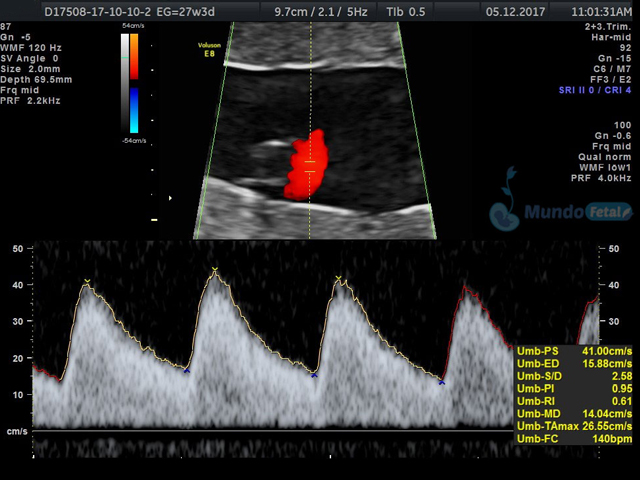

Se recomienda de 32-34 semanas, realizando valoración de crecimiento armónico (4 medidas específicas), valoración anatómica, líquido amniótico, flujos sanguíneos fetales y placentarios perfilando el bienestar fetal hacia el final de embarazo.